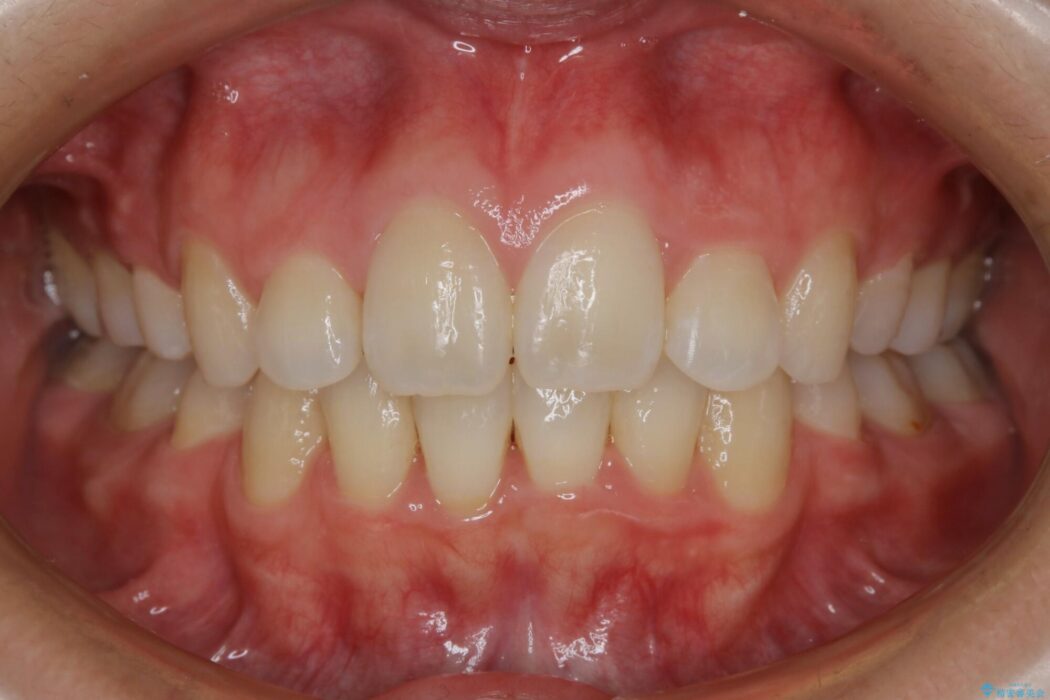

治療後について

顔貌のビフォーアフターでもわかるように口元の出っ張りが改善され、患者様にはとても喜んでいただけました。

横顔であったり笑った時の印象にも変化があるため、同様のお悩みを抱えている方はぜひご相談ください。